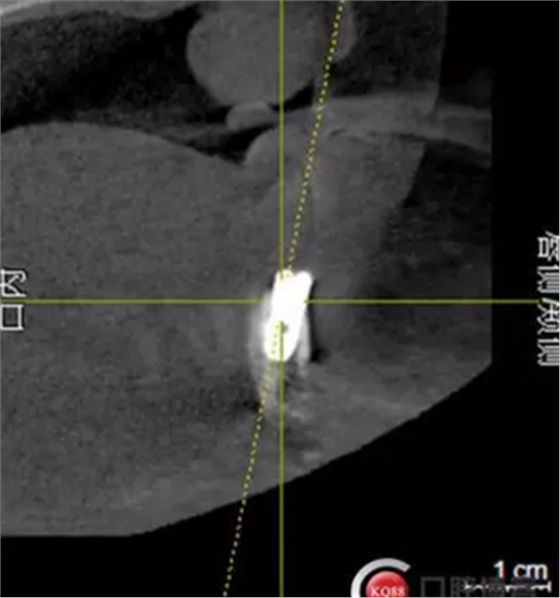

2)術前準備及手術過程,測量血壓及血糖,簽種植知情同意書;嚴格遵循無菌操作,局麻下采用微創(chuàng)技術于323436分別植入osstem4.0X10,4.0X10,4.5X7; 434446分別植入osstem4.0X1O,4.0X10,4.5X7.初期穩(wěn)定性均達到了35N.CM以上;嚴密縫合,止血,種植體位點和方向與設計一致。

4)三個月后行種植二期手術并拔除33殘冠,于34364346種植體接入成品基臺,調改活動義齒做一個改良式的套筒冠覆蓋義齒。

戴牙:試戴,拍片確定邊緣密合后調整咬合,試戴一周后患者適應,咬合良好,基臺加力30N.CM,粘接劑粘固,去除多余粘結劑,拍片確定有無粘接劑殘留,并進一步微調咬合